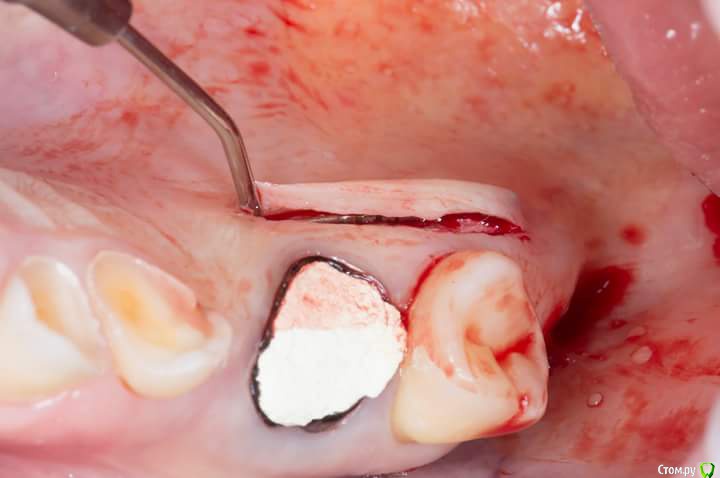

Sampson Опубликовано 3 июля, 2018 Поделиться Опубликовано 3 июля, 2018 1. Забор трансплантата из области 16-17Ушивание2.пластика предверия штрипсой по Урбану3. Установка 2 импланта Adin rpУшивание4.удаление 16. Prf в лунку,поверх губка Альванес. 7 Ссылка на комментарий